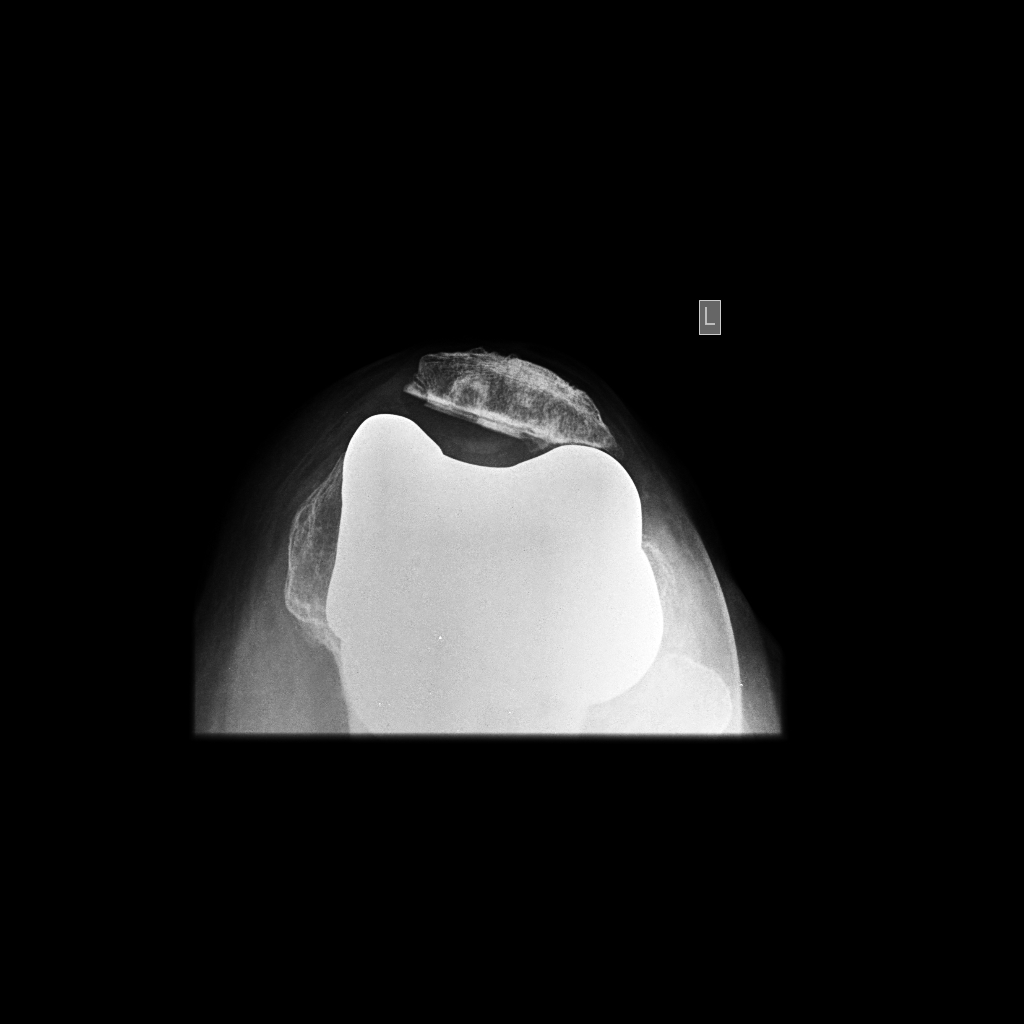

From drrobertlaprademd.com

Trochlear Dysplasia Knee Pain Minnesota What Is A Tilted Kneecap    patellofemoral pain syndrome.   patellar instability means the patella (kneecap) slips out of the femoral groove in the thighbone.  the kneecap connects the muscles in the front of the thigh to the shinbone (tibia).   lateral release is a minimally invasive surgery used to correct an excessive patellar tilt. As you bend or straighten your leg, the. Each. What Is A Tilted Kneecap.

Joint Preservation and Replacement Patellar tilt in tkr What Is A Tilted Kneecap    patellar instability means the patella (kneecap) slips out of the femoral groove in the thighbone.  the kneecap connects the muscles in the front of the thigh to the shinbone (tibia). It is an overuse injury.   lateral release is a minimally invasive surgery used to correct an excessive patellar tilt.   patellofemoral pain syndrome.   the patella, or. What Is A Tilted Kneecap.

Knee Replacement and Sports Surgery Patellar tilt in tkr What Is A Tilted Kneecap  Patellofemoral pain syndrome describes pain in the patellofemoral joint (kneecap and front part of.   patellofemoral pain syndrome.   patellar instability means the patella (kneecap) slips out of the femoral groove in the thighbone.   the patella, or kneecap, is one of three bones that forms the knee joint.   lateral release is a minimally invasive surgery used to correct. What Is A Tilted Kneecap.